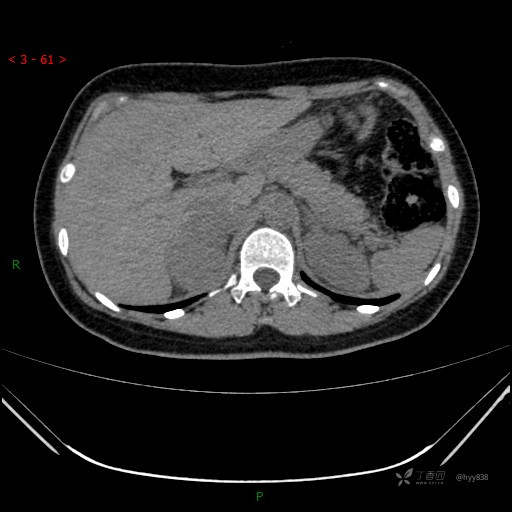

辅助检查:CT

静脉期